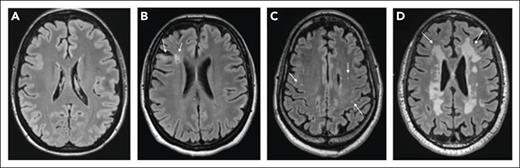

SCI were observed in 18 of 36 (50%) participants who completed the study MRI. None of the participants had a nonsilent infarct at the time of evaluation. Figure 2 shows examples of varied brain MRI findings in patients with iTTP, including normal imaging (Figure 2A), SCI manifesting as small FLAIR hyperintense lesions (>3 or 5 mm in length) involving the cortical or subcortical region and deep white matter (Figure 2B), smaller scattered punctate FLAIR hyperintense lesions in the subcortical and deep white matter attributed to nonspecific chronic small vessel ischemic changes (Figure 2D), and extensive and confluent FLAIR hyperintensity in the periventricular and deep white matter (Figure 2C). Among patients with SCI, 8 of 18 (44.4%) had a history of overt stroke, including 3 patients who had stroke during an acute iTTP episode, whereas 10 of 18 (55.6%) did not have a history of clinically overt stroke. Thus, even among some patients with a clinical history of stroke, new SCIs were detected with study MRIs. Figure 3 shows such an example of a 46-year-old woman (patient 1) who had an initial clinical MRI performed for dizziness that started during the iTTP episode but persisted for 3 months after achieving clinical remission; this MRI showed evidence of small chronic infarcts in bilateral cerebellar hemispheres. A research MRI performed 3 years later demonstrated multiple, small, chronic cortical infarcts that were new, without corresponding focal neurological deficits. She did not have any intercurrent iTTP episodes between the 2 MRIs. Her ADAMTS13 activity had been monitored every 3 months in remission and ranged from 38% to 100% (average, 72%; reference range, 70%-150%). Although she did not receive preemptive rituximab, she did receive immunosuppression for systemic lupus that might have led to improvement in ADAMTS13 activity.

Brain MRI findings in patients with iTTP (representative images). Normal MRI without ischemic findings (A), small FLAIR hyperintense foci (>3-5 mm in length, arrows) in the cortical/subcortical region and deep white matter (B), punctate FLAIR hyperintense lesions (arrows) in the white matter (C), and confluent FLAIR hyperintensity (arrows) in the periventricular and deep white matter (in a patient without overt neurologic findings) (D).